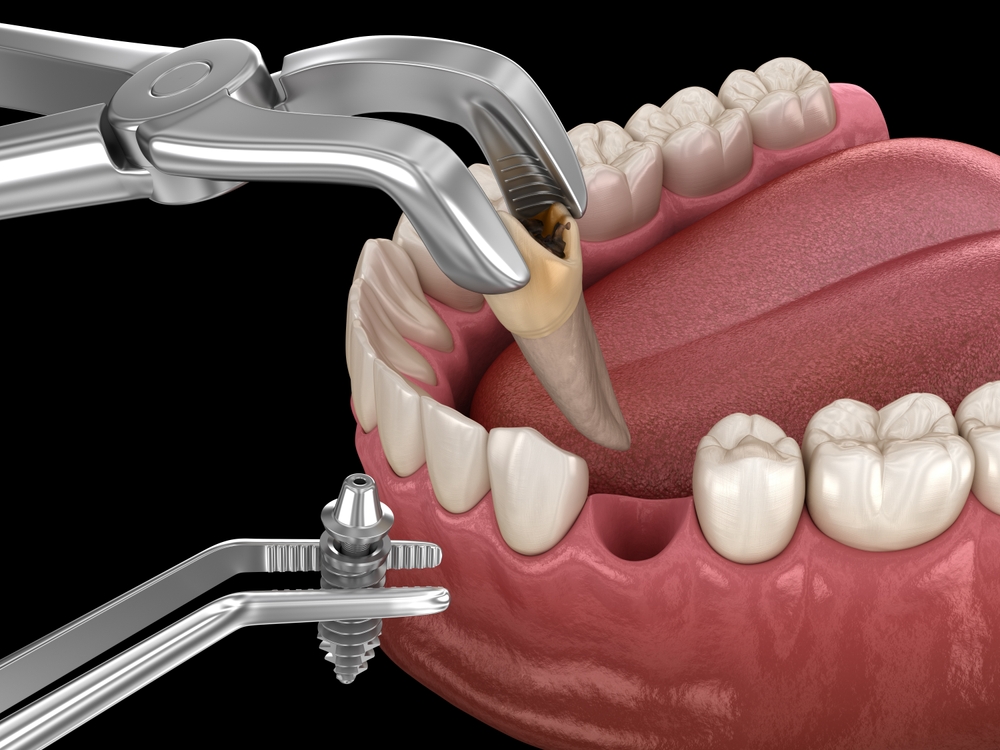

임플란트 염증이 생기는

과정은 다양해요.

임플란트 주변은 자연 치아와

구조가 다르기 때문에 조금만

관리가 느슨해져도 임플란트 염증과

같은 불편함이 나타날 수 있습니다.

또한, 사용 기간이 길어지면 주변

잇몸이나 뼈의 변화가 서서히

일어나기 때문에 유지 관리를

더 신경 써야 합니다.